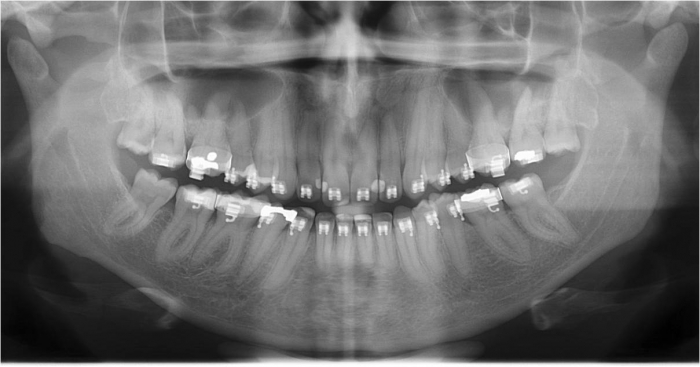

Raio x inicial

Raio x após a cirurgia